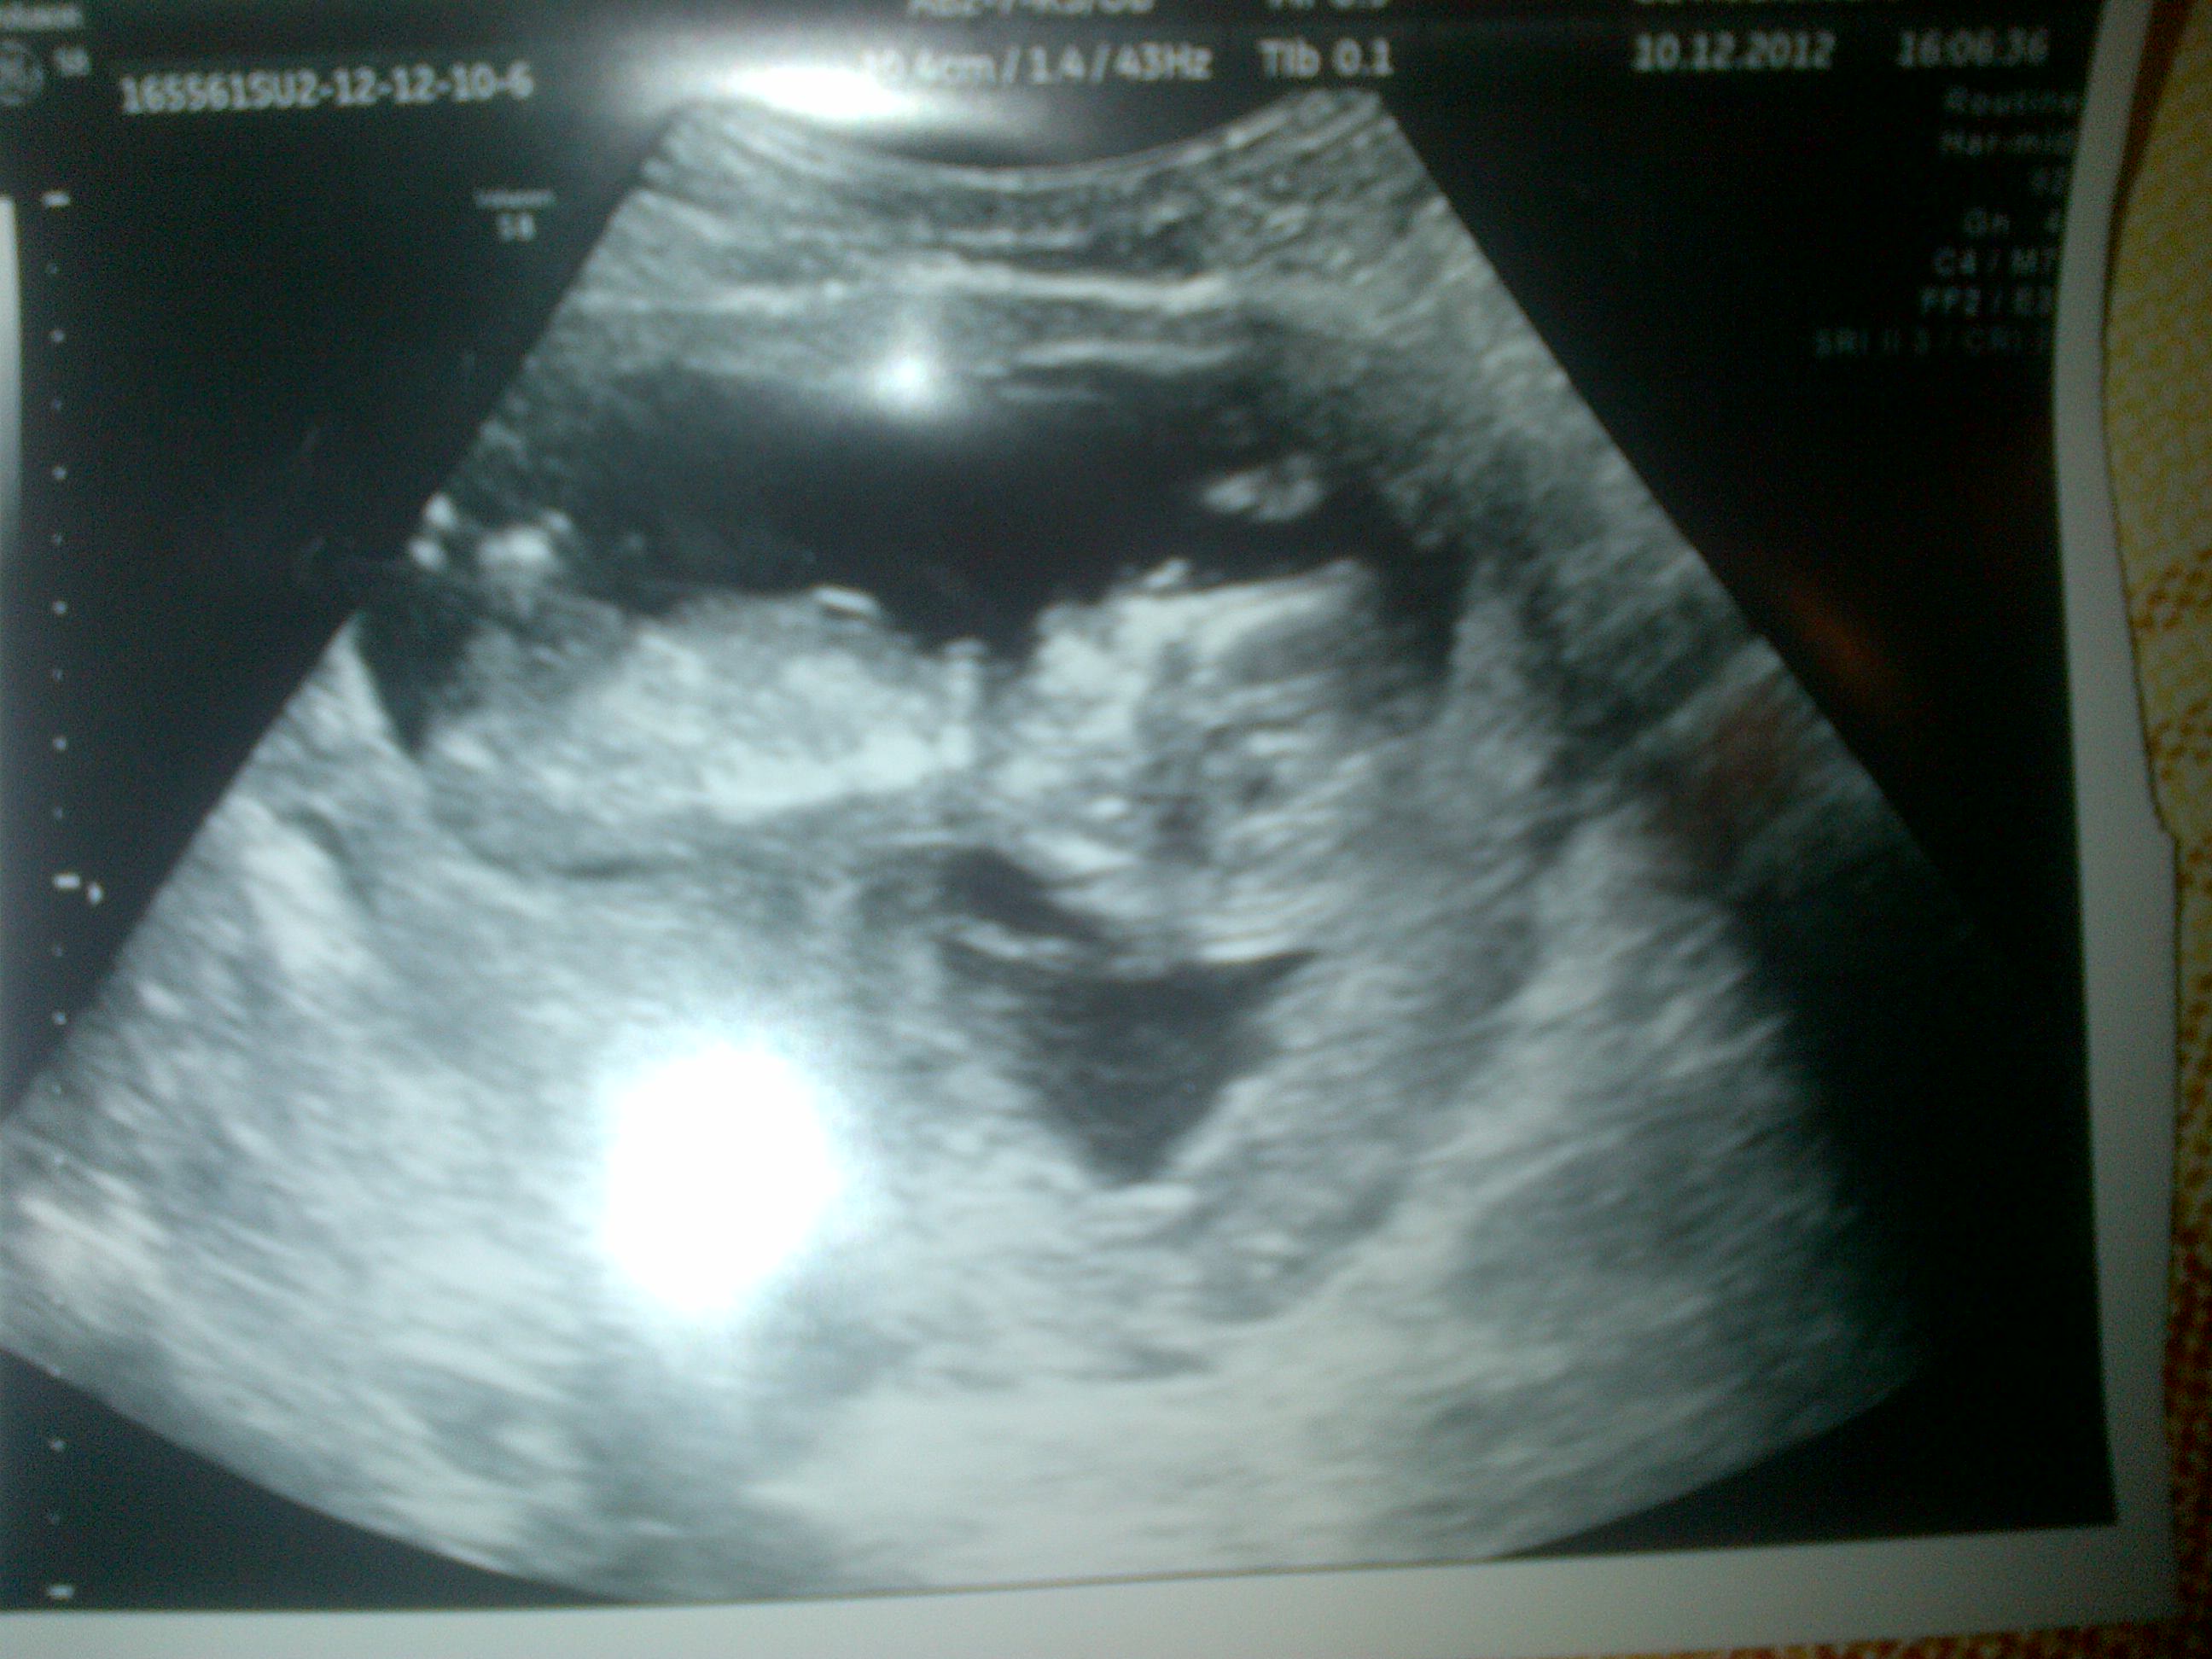

Hi everyone, this is my first time on this site, so new too iy, got a pic of my scan, would love some guesses x x x